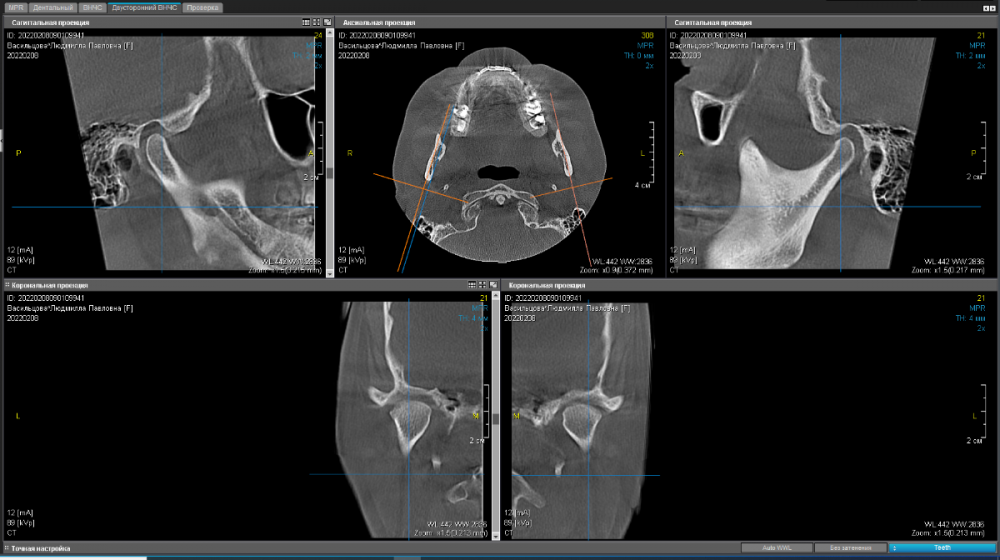

Произведено: функциональная диагностика.  Выставлено новое терапевтическое положение нижней челюсти. Изготовлен байт(силиконовая накуска) и пациент отправлен на КТ

КТ ДО(до диагностики):

336494961_.thumb.png.684f55cf9298867e9822af0a23afacd8.png

КТ ПОСЛЕ(с байтом в полости рта):

1179766551_.thumb.png.b843c7b5a257dab69d353cd58d83e3fe.png

В целом хорошо. Пальпация стала безболезненной, из биламинарной зоны мыщелок убрали - одни плюсы. Изготовили капу, составили план лечения и погнали..